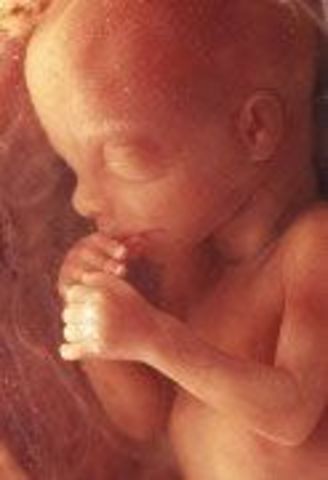

• Week 12: Fingernails and Toenails Appear

Week 12: Fingernails and Toenails Appear

Fetus is now 2.5 inches in length and weighs about 0.7 ounce, feet are almost half an inch long, fetus starts moving spontaneously, face is beginning to look like a baby's face, pancreas is functioning and producing insulin, fingernails and toenails appear, baby can suck thumb and get hiccups